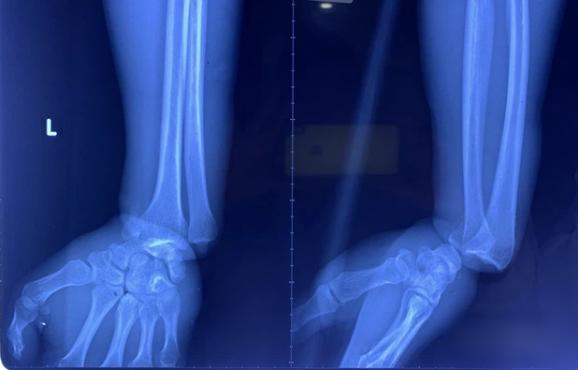

Sau khi chụp X-quang tại Bệnh viện Chấn thương chỉnh hình TP HCM, các bác sĩ ghi nhận anh L. có 1 vòng siết chặt ở cổ tay và hết 1 vòng chu vi cổ tay.

Hình ảnh chụp X-quang của anh L.

Hậu phẫu, các bác sĩ chẩn đoán bệnh nhân bị gãy trật khớp cổ tay trái, dập tắc bó mạch thần kinh trụ, dập động mạch quay, dập thần kinh giữa, dập nát các gân - cơ gân duỗi các ngón...